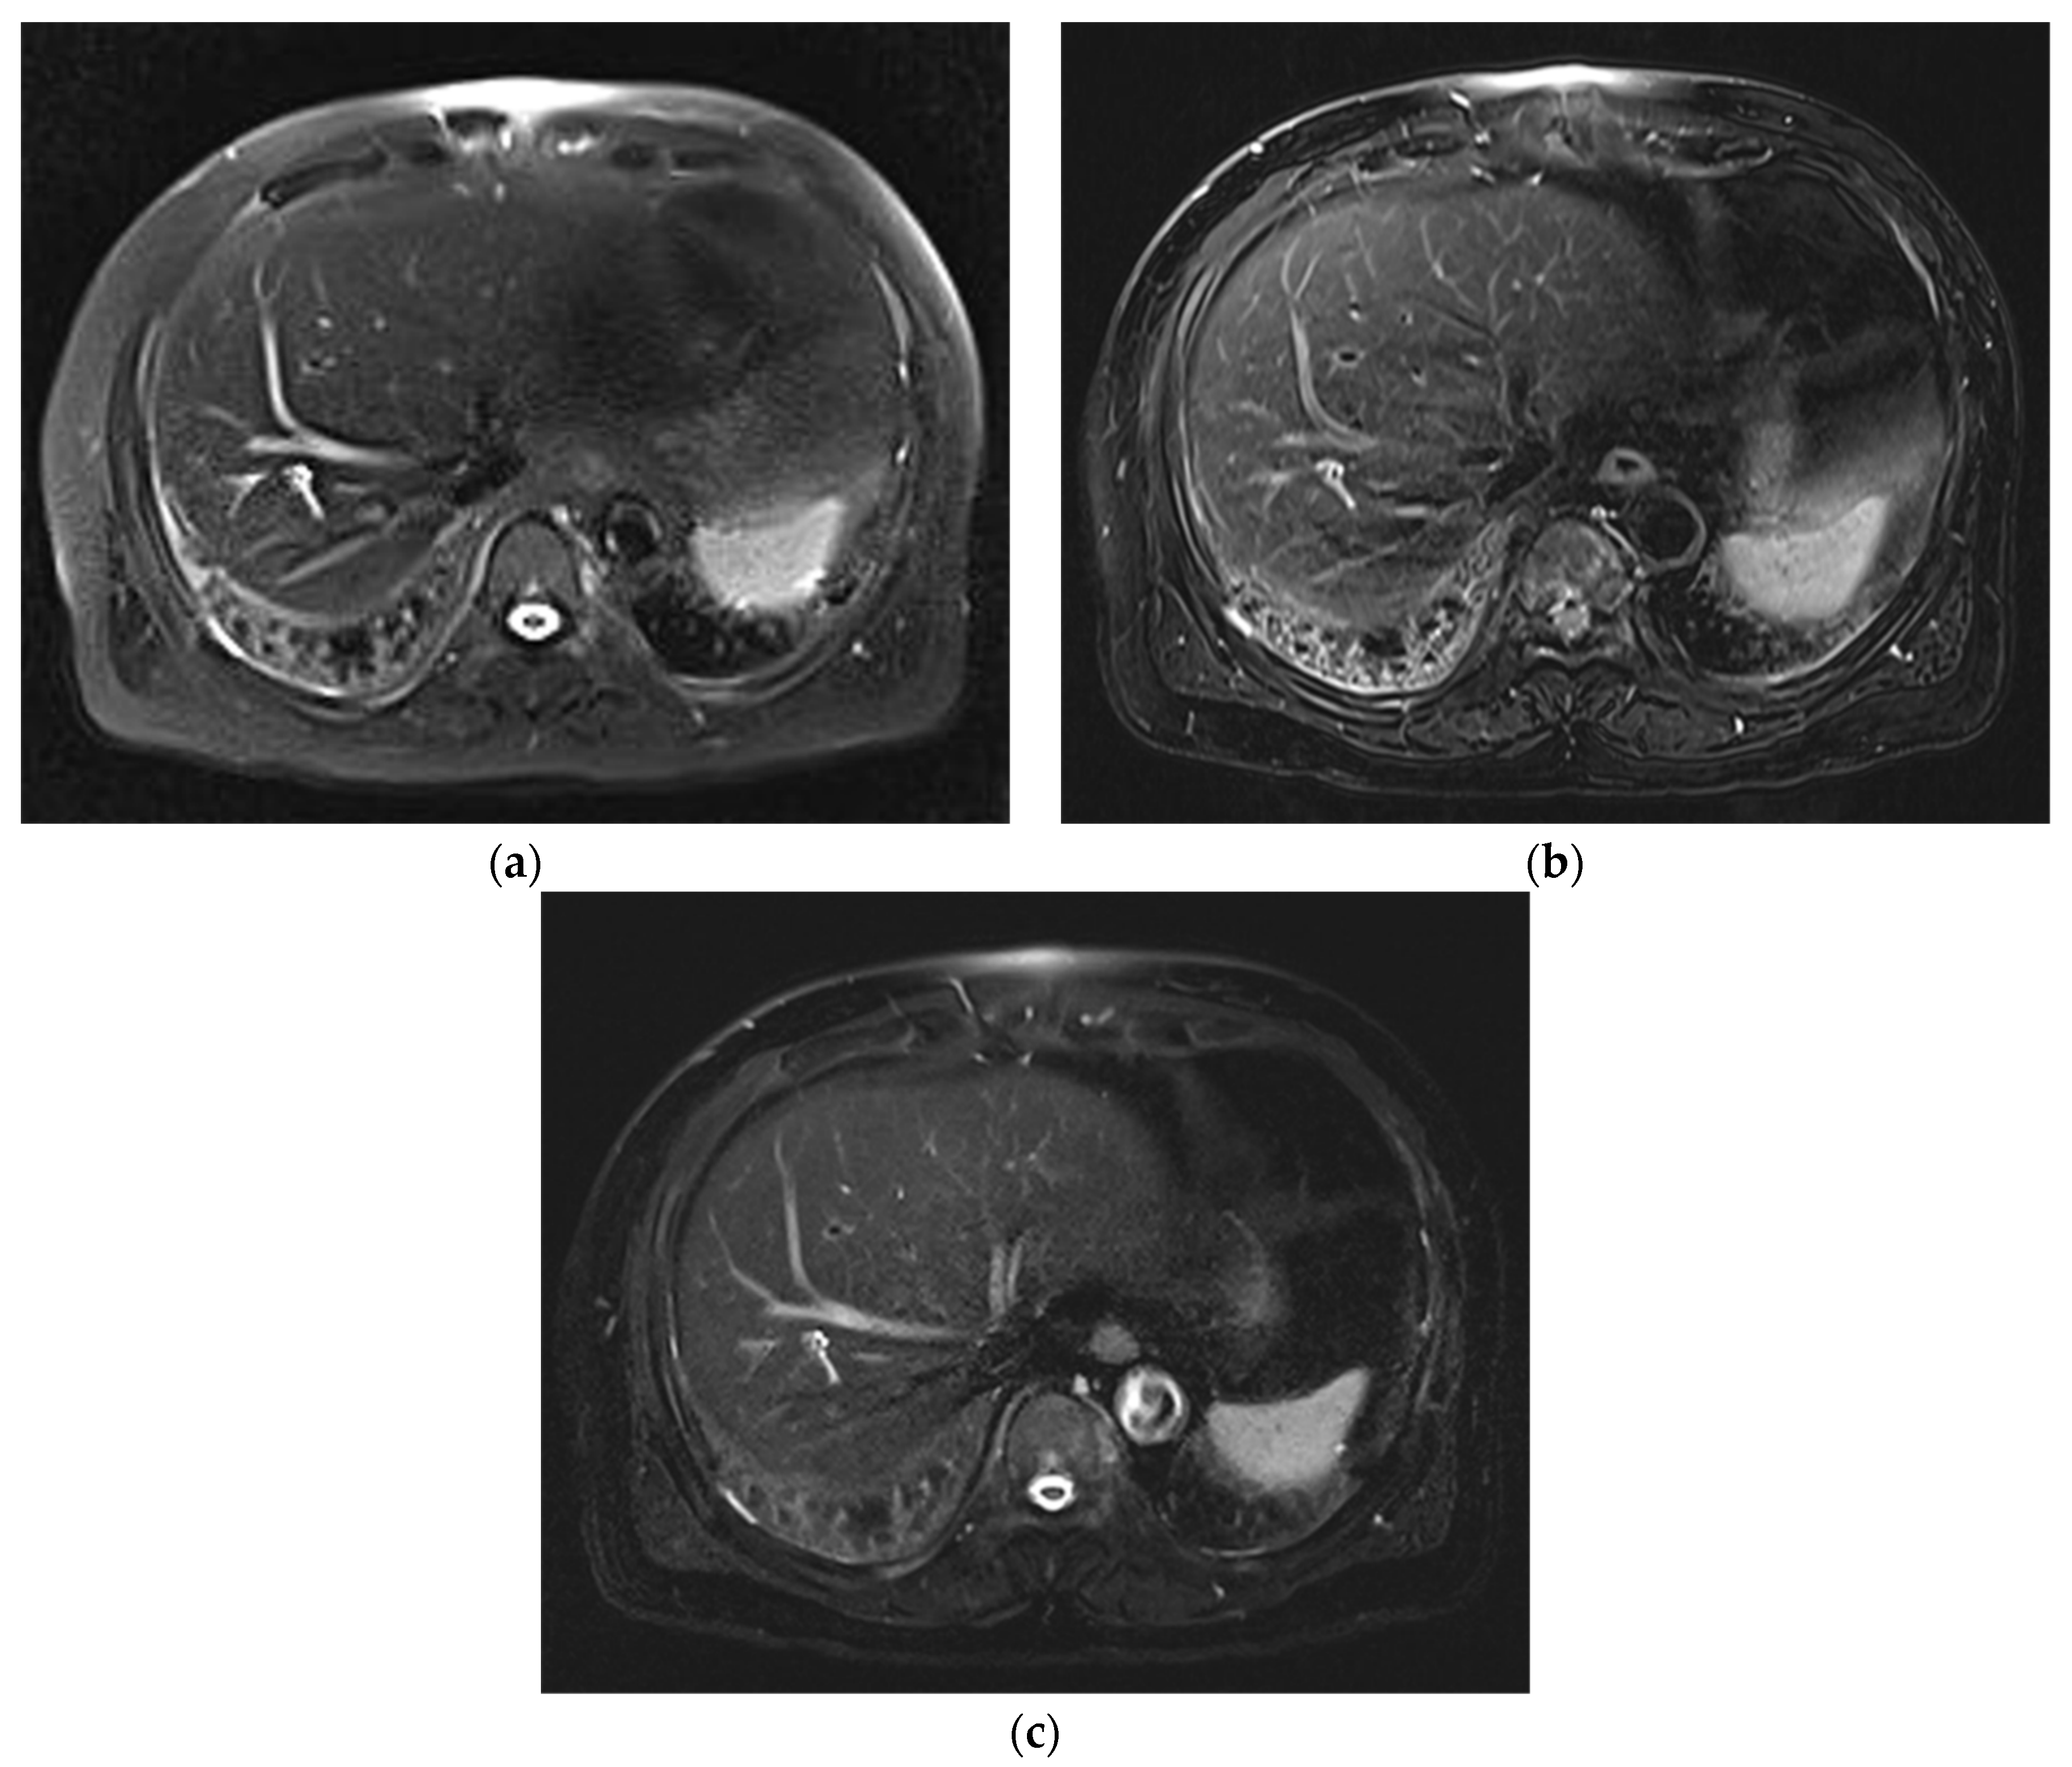

Improved Single Breath-Hold SSFSE Sequence for Liver MRI Based on Compressed Sensing: Evaluation of Image Quality Compared with Conventional T2-Weighted Sequences

3. Results

3.1. Subjective Image Quality

3.2. Lesion Assessment

4. Discussion